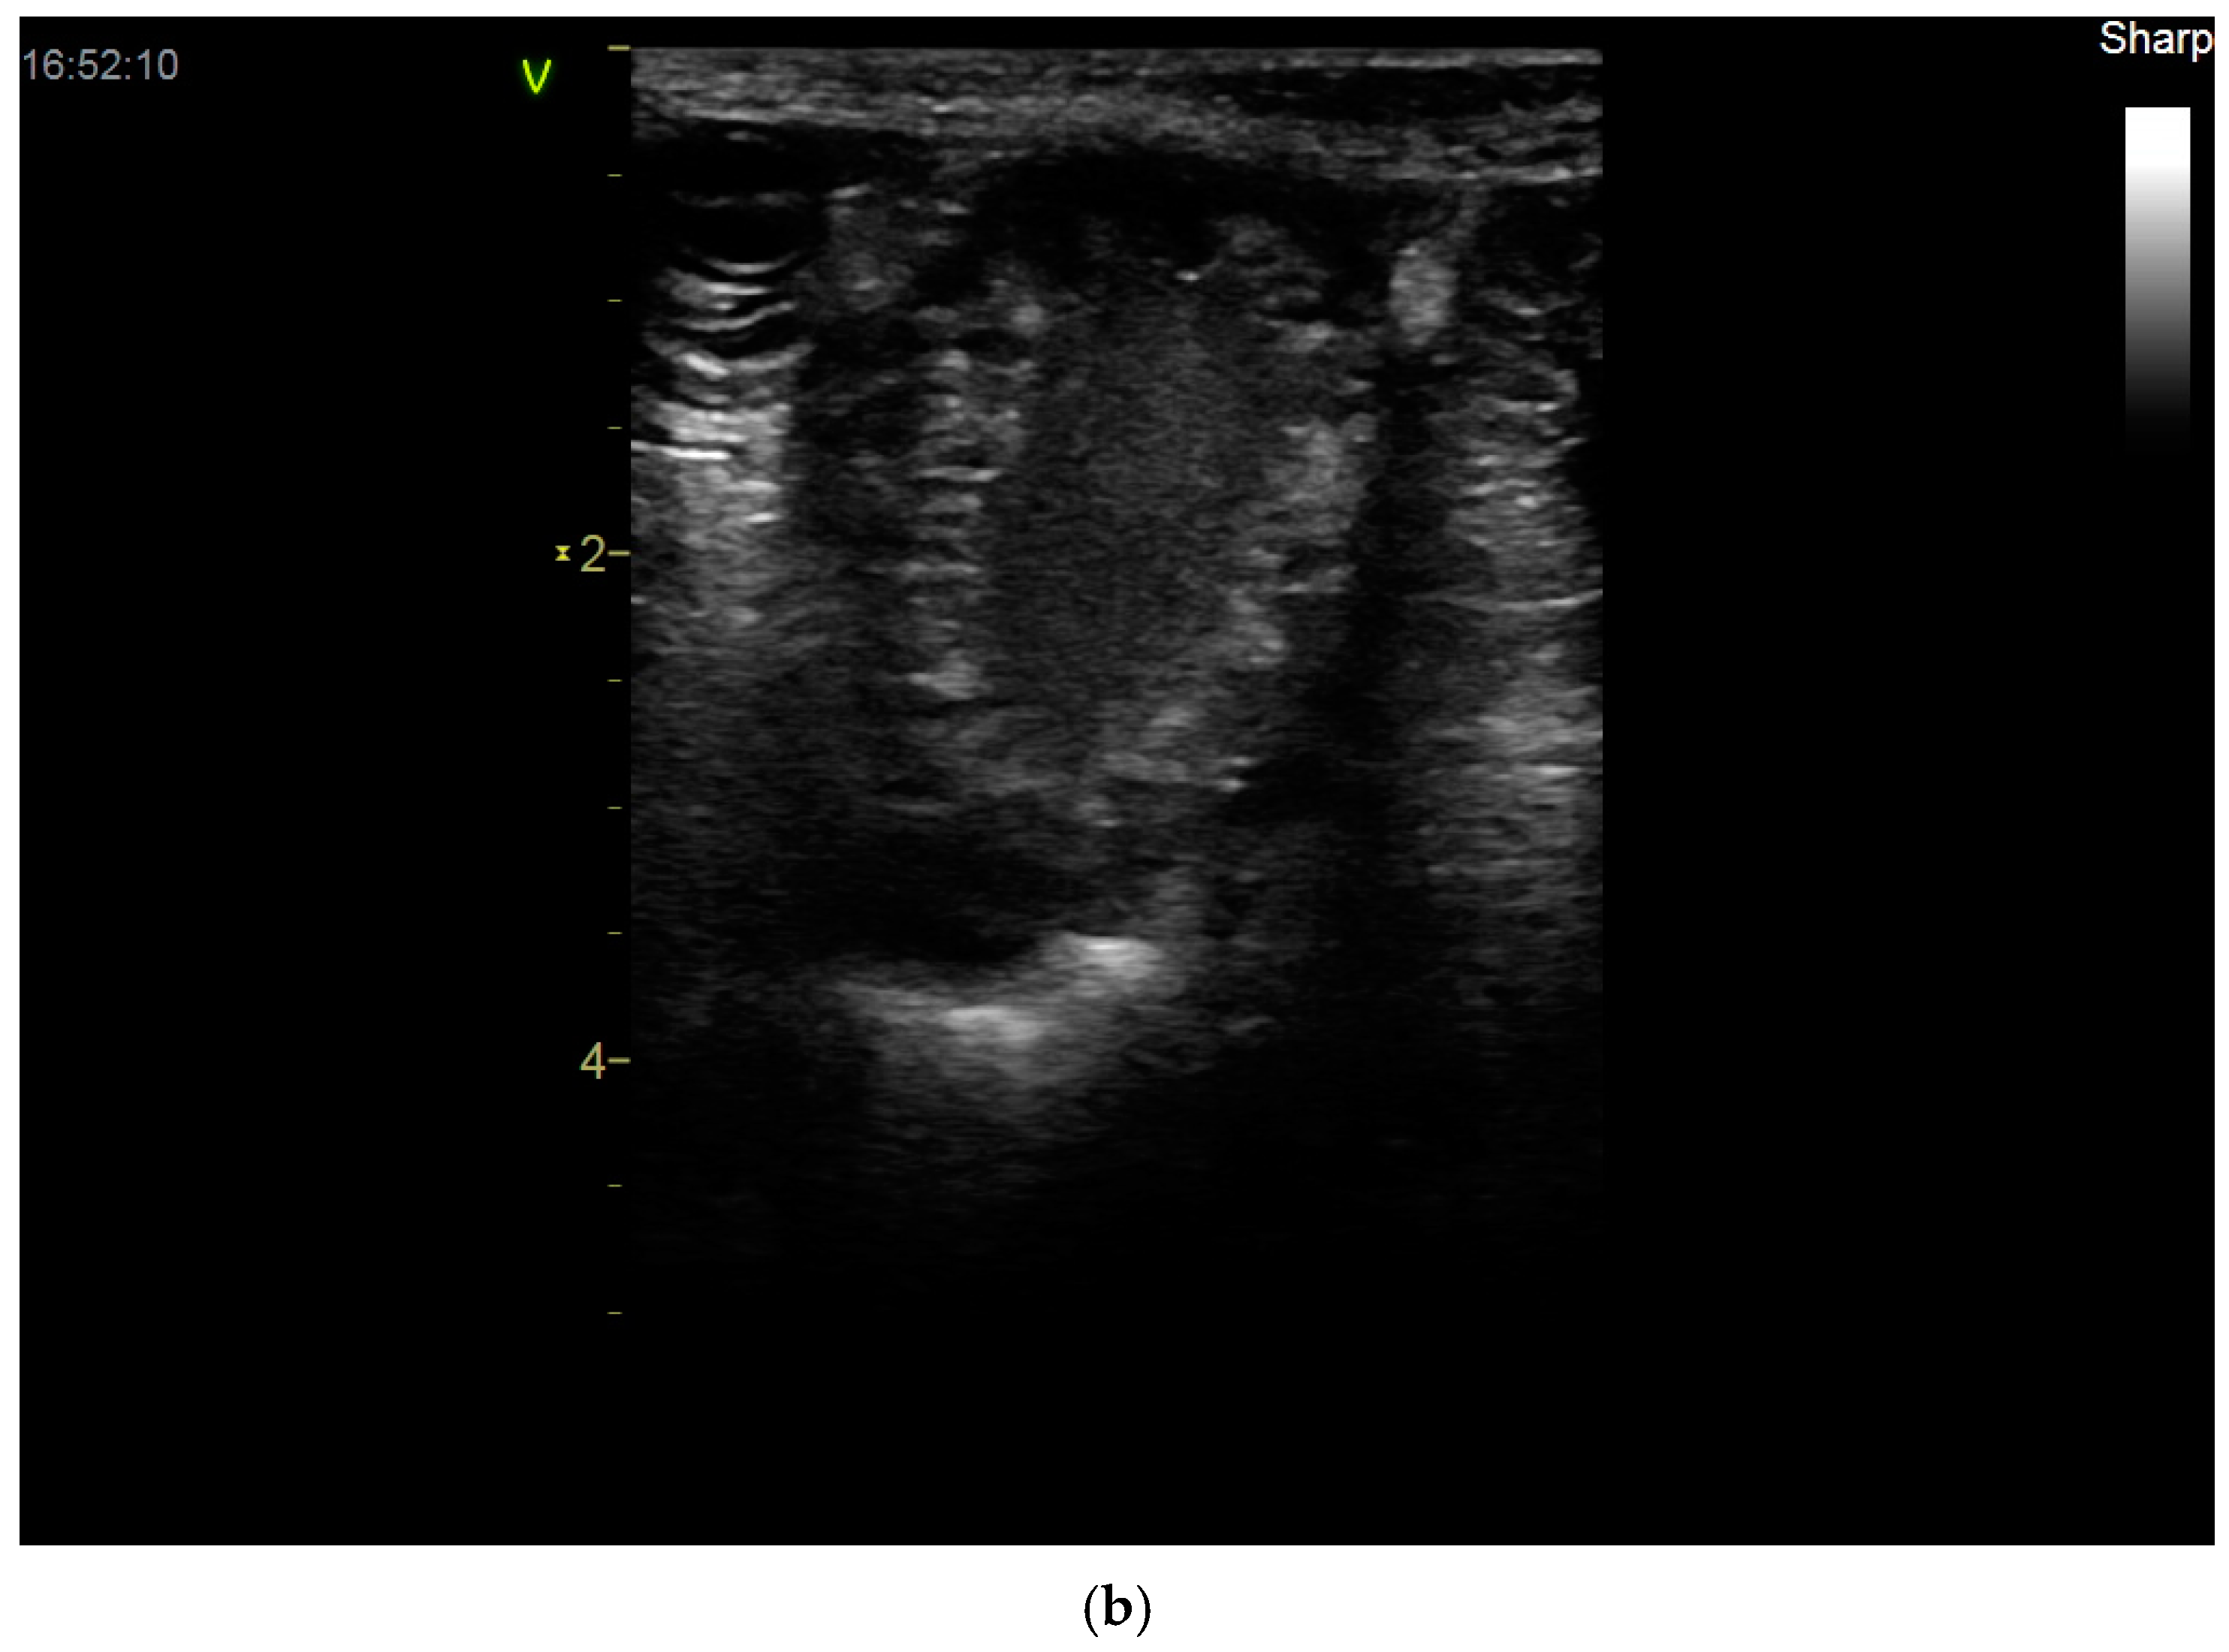

2.3. Uterine Pathology